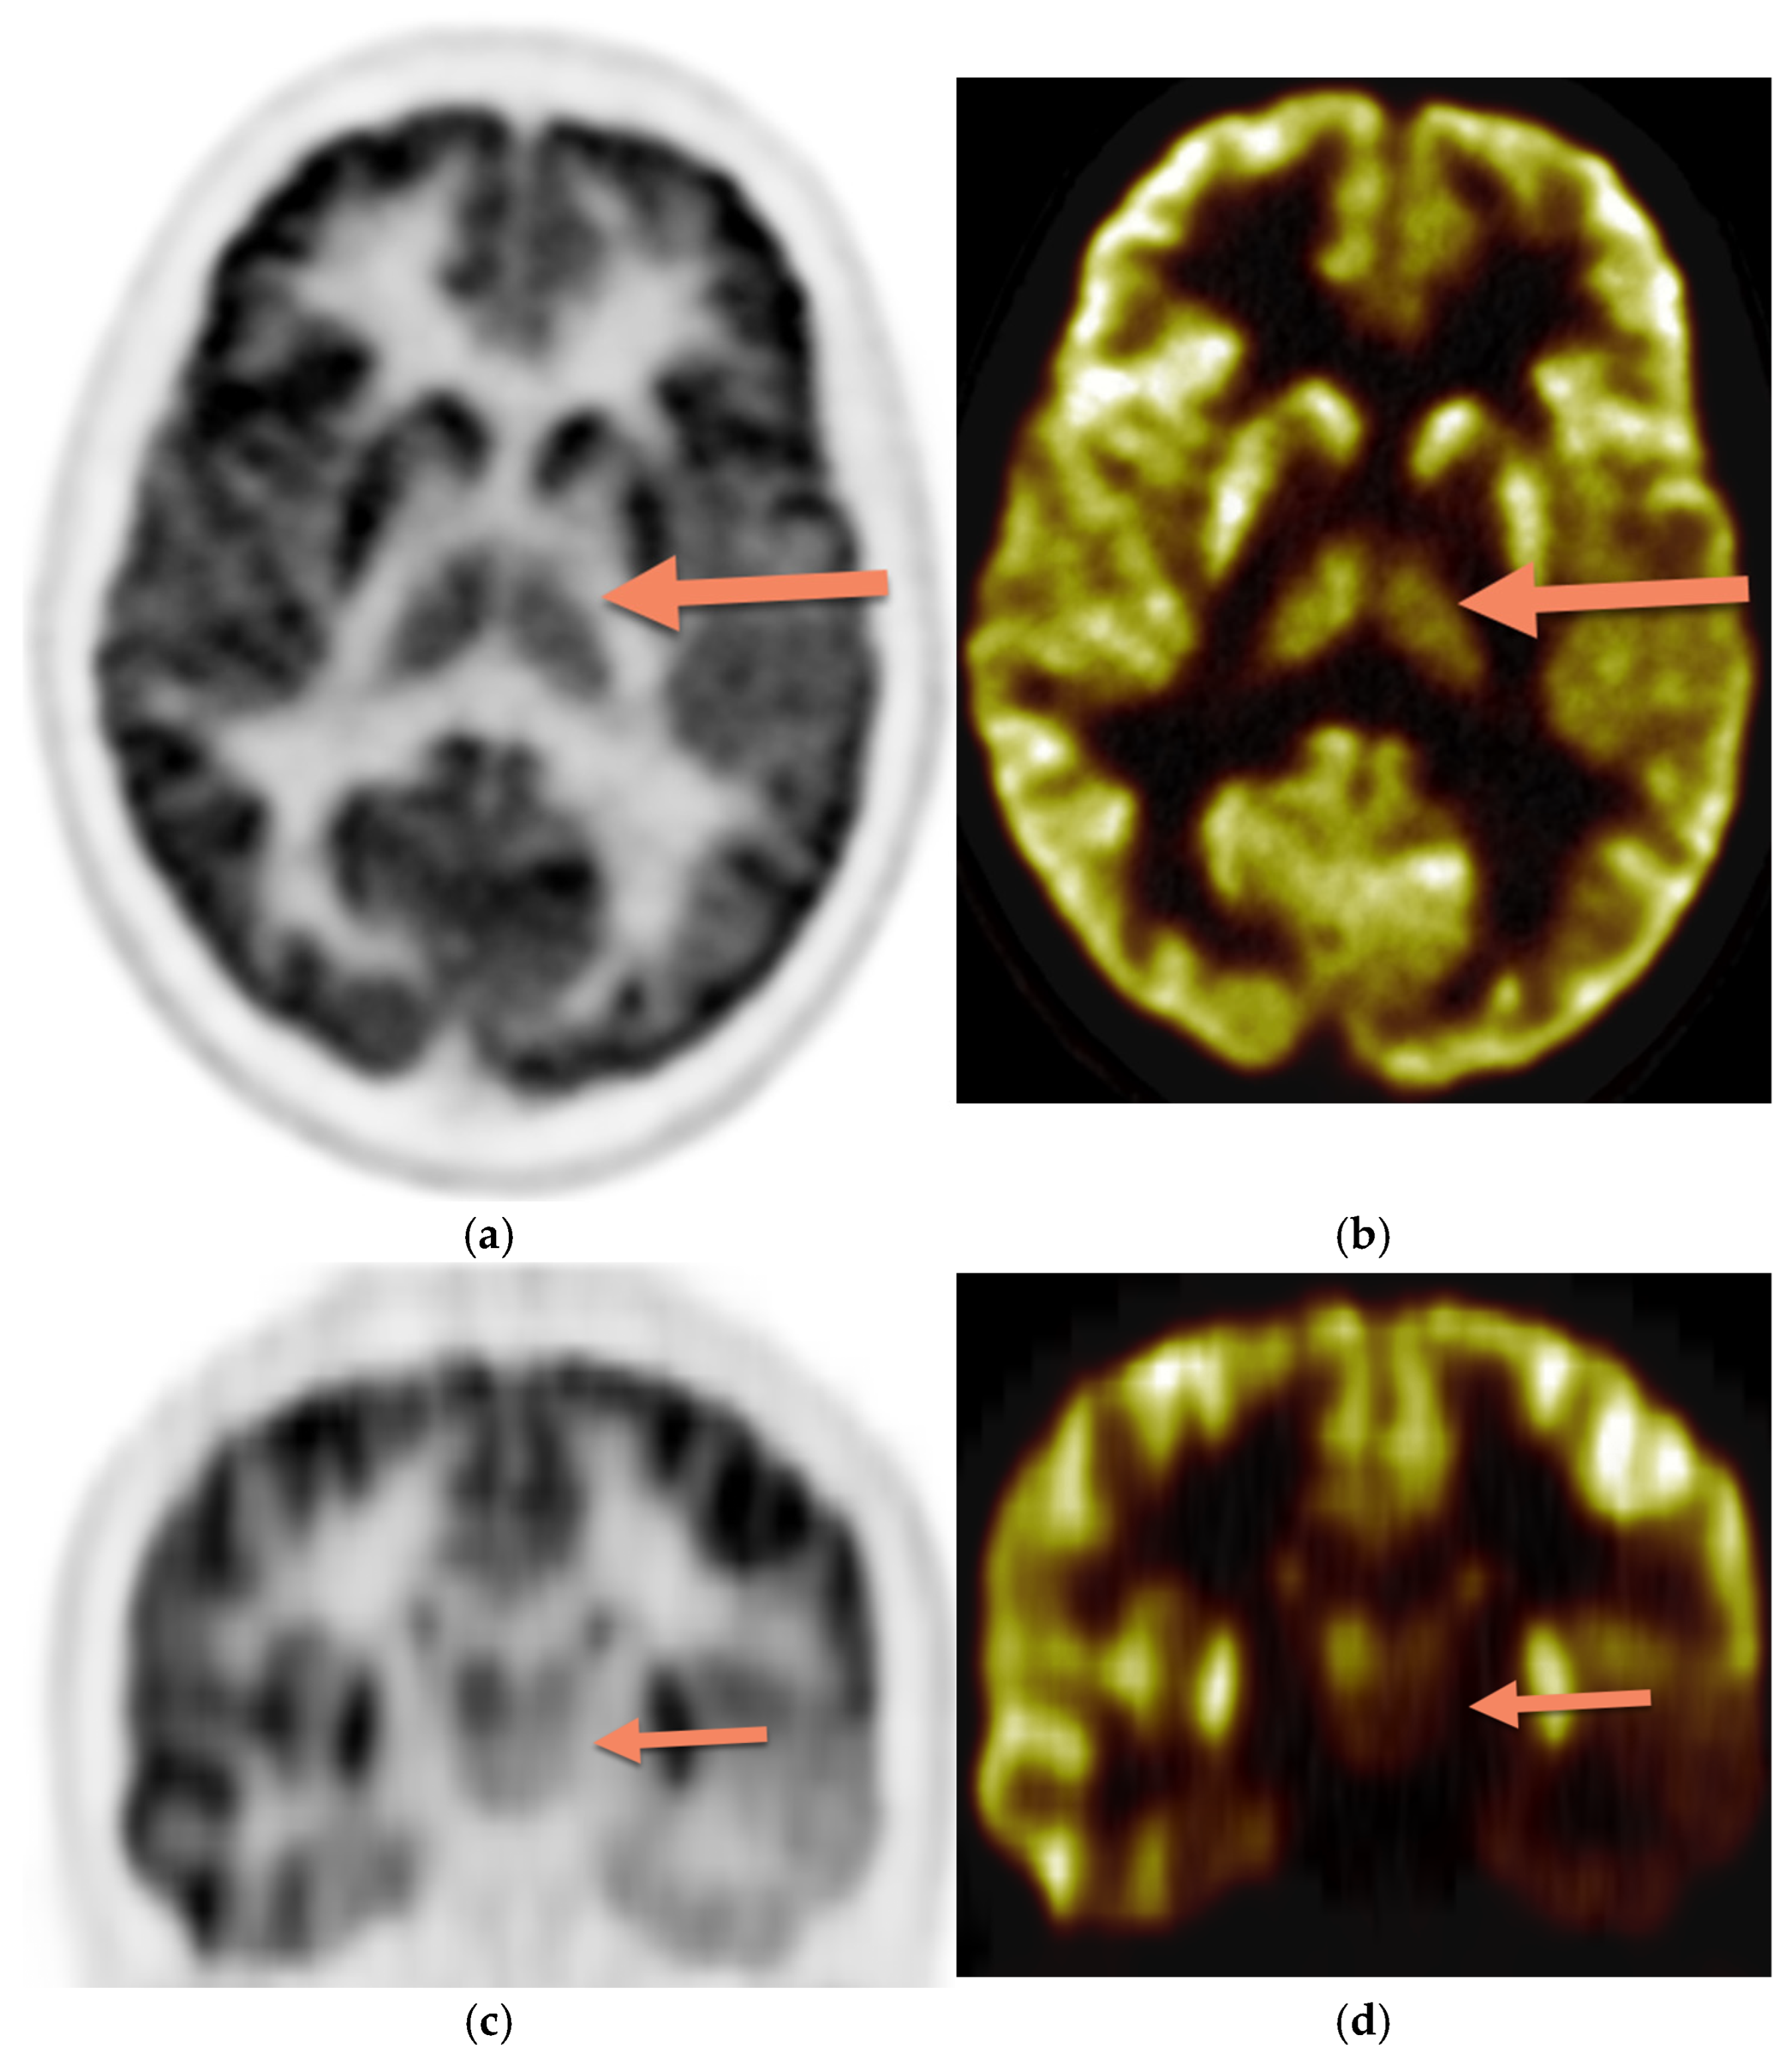

The PET images were reviewed and interpreted by two expert nuclear medicine physicians who were blinded; if there was any discrepancy, there was a consensus. Visual analysis was used to identify the location of the hypometabolic epileptogenic zone compared to the cortical activities. The metabolic activity of the bilateral thalamus was assessed qualitatively (thalamic 18F-FDG uptake in relation to the cerebral cortex and contralateral thalamus). Normal thalami are symmetric with metabolic activity similar to the normal cortex (Figure 2). Figure 3 demonstrates asymmetric decreased activity in the left temporal lobe as well as reduced left thalamus uptake.

Figure 3. Brain 18F-FDG PET, (a) (sagittal grey scale), (b) (sagittal rainbow color), (c) (coronal grey scale), and (d) (coronal rainbow color) in a 13-year-old female with asymmetric decreased activity in the left temporal lobe. The uptake of the left thalamus is also reduced (arrow) compared with the contralateral side.